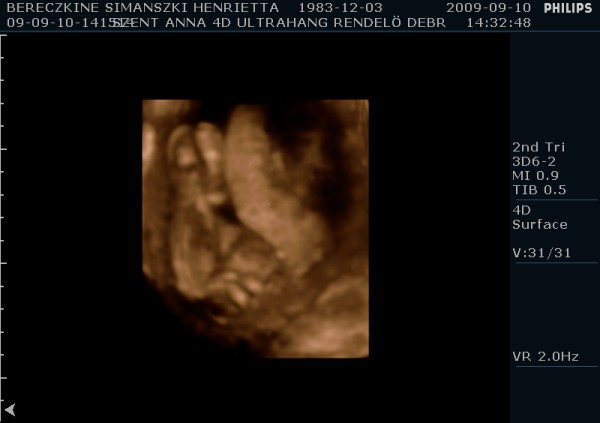

Megjöttem én is ismét, tettem fel képeket. A párom ragaszkodott hozzá, hogy kérjünk DVD-t, így hát átkapcsoltak 4D-be is. Kb. 10-15 perc lett a dvd, nagyon jópofa, látszik mindene. Mozognom, köhögnöm kellett nekem is, hogy a baba felébredjen, de amikor ébren volt, hihetetlen mit művelt. Egyik helyről a másikra átment, az első képen épp ez látható. :-) Ott a lábai vannak alul, a térdei nagyon jól látszanak. Épp ekkor rúgta át magát egy neki kényelmesebb pozícióba. :-)

Egyébként nálunk is megszólalt a nő, hogy nagyon fiúnak tűnik, de a párom rászólt, hogy ő nem akarja tudni. :D

Ami még érdekes, hogy tegnap 49mm-nek mérték, ma pedig 55mm-nek a CRL-t. A nyaki redő tegnap 1,4mm volt, ma az 1,3mm lett, itt nem nagy a különbség.